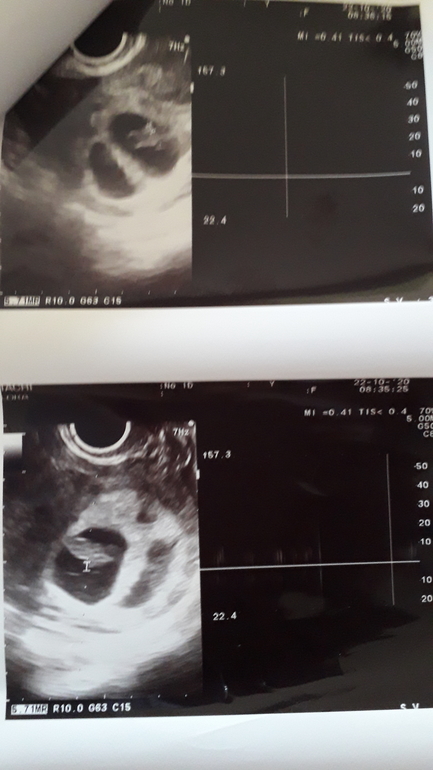

❤❤ 8н2д

поздравляю))) это у вас ди-ди, получается?)

дихориальная диамниотическая, если я правильно понимаю, два пя, два эмбриона)))

Кукуся, да разнояйцевые по-простому 😁..посадили 2, они и остались со мной.🙏

Криоперенос повторнозамороженого эмбриона 7ДПП крио, пятидневка